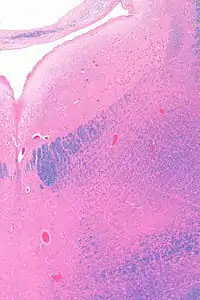

![]() Micrograph showing the locus coeruleus. HE-LFB stain. | |